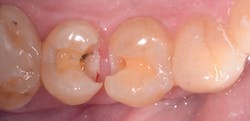

The placement of posterior composites has often troubled dentists. They can be time-consuming, technique-sensitive, and costly to do. There are a number of composites on the market that claim to be "bulk fill," implying we can reduce or eliminate multiple increments of applications. If that's the case, we would be able to tackle our operative dentistry more efficiently and more predictably. Fortunately, some bulk fill composites are "true" bulk fill composites that have the necessary ingredients to deliver on that promise. Let's look at the trials and tribulations of placing posterior composites and compare them to using Tetric EvoCeram Bulk Fill.

First, we need to consider how much time it takes to do a posterior composite. Posterior composites require a layered incremental curing strategy. Each layer can only be 2mm thick and needs to be cured for 10-20 seconds per layer. Due to the patented Ivocerin initiator with Tetric EvoCeram, you can fill up to 4mm with one placement and cure this for 10 seconds to get complete cure to the depth of the preparation. That is a time savings of 30-60 seconds per tooth. While for one tooth this may not seem like a lot, it quickly adds up when you start doing quadrant dentistry.

The stress relievers that are part of the new filler technology mean I am putting less stress on the composite, which leads to a number of advantages as well. Postoperative sensitivity is decreased due to less stress on the tooth. Also, the margins do not get the dreaded white line, indicating the bond is breaking down from too much shrinkage.

Another property to look for in your bulk fill is whether or not it can blend with more than one tooth shade. The Tetric IvoCeram Bulk Fill IVA shade works for any shade in the "A" family. If I have an A1, I grab the IVA. If I have an A3, I grab the IVA. This simplifies my inventory and makes my assistant's life easier. It also means I don't have a bunch of half-empty shades left over. Also, because these fit into any composite gun, I don't have any special equipment I need to buy or transport between operatories.